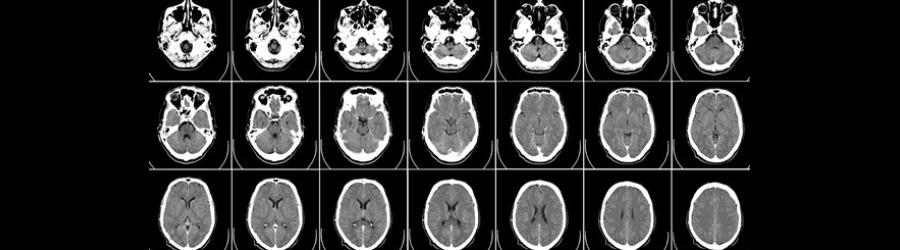

Research in Psychology and Neuroscience progresses rapidly; we discover more about how we learn and how our memories work. This online course will provide a guided tour through the brain, looking at the changes that occur on a cellular level when we learn new information or store a memory. We will examine the way the brain changes from child to teenager to adult, and how these affect the way we learn and remember information. By understanding more about the way memories are stored and recalled, we can explore different ways to help improve this process, at any stage of our lives.

Purpose: To introduce students to the neuroscience of learning and memory, and our limitations in its understanding. We will cover the reconstructive nature of memories, false memories, and their implications. By studying this week the students should have:

- Understood what neurons and synapses are, and their role in memory formation.

- Know the main brain regions implicated in memory and learning.